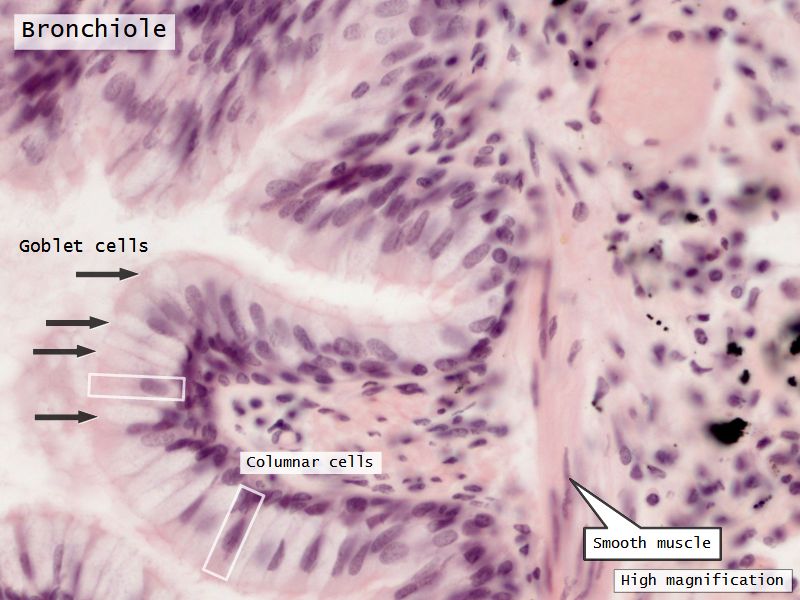

Respiratory epithelium

- Pseudostratified

- Ciliated

- Columnar

- Epithelium with

- 4 Cells

- Ciliated columnar cells

- Non-ciliated columnar cells

- Goblet cells

- Basal cells